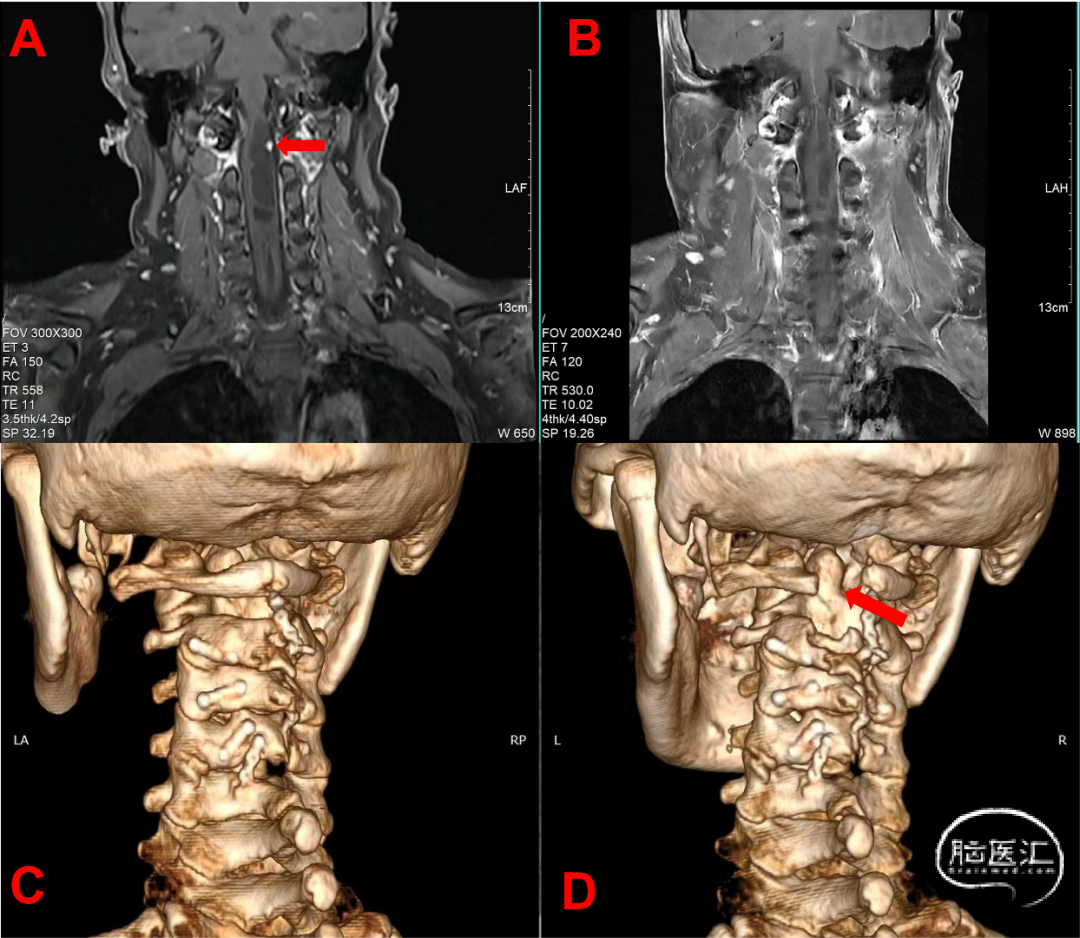

术后患者状态平稳,四肢肌力5级,肌张力正常,左侧肢体浅感觉减退较术前好转。复查MRI提示颈髓术后,颈1水平强化结节已切除(图4B)。术后CT-VRT重建提示C1后弓及C2左侧椎板上缘部分缺如(图4D)。